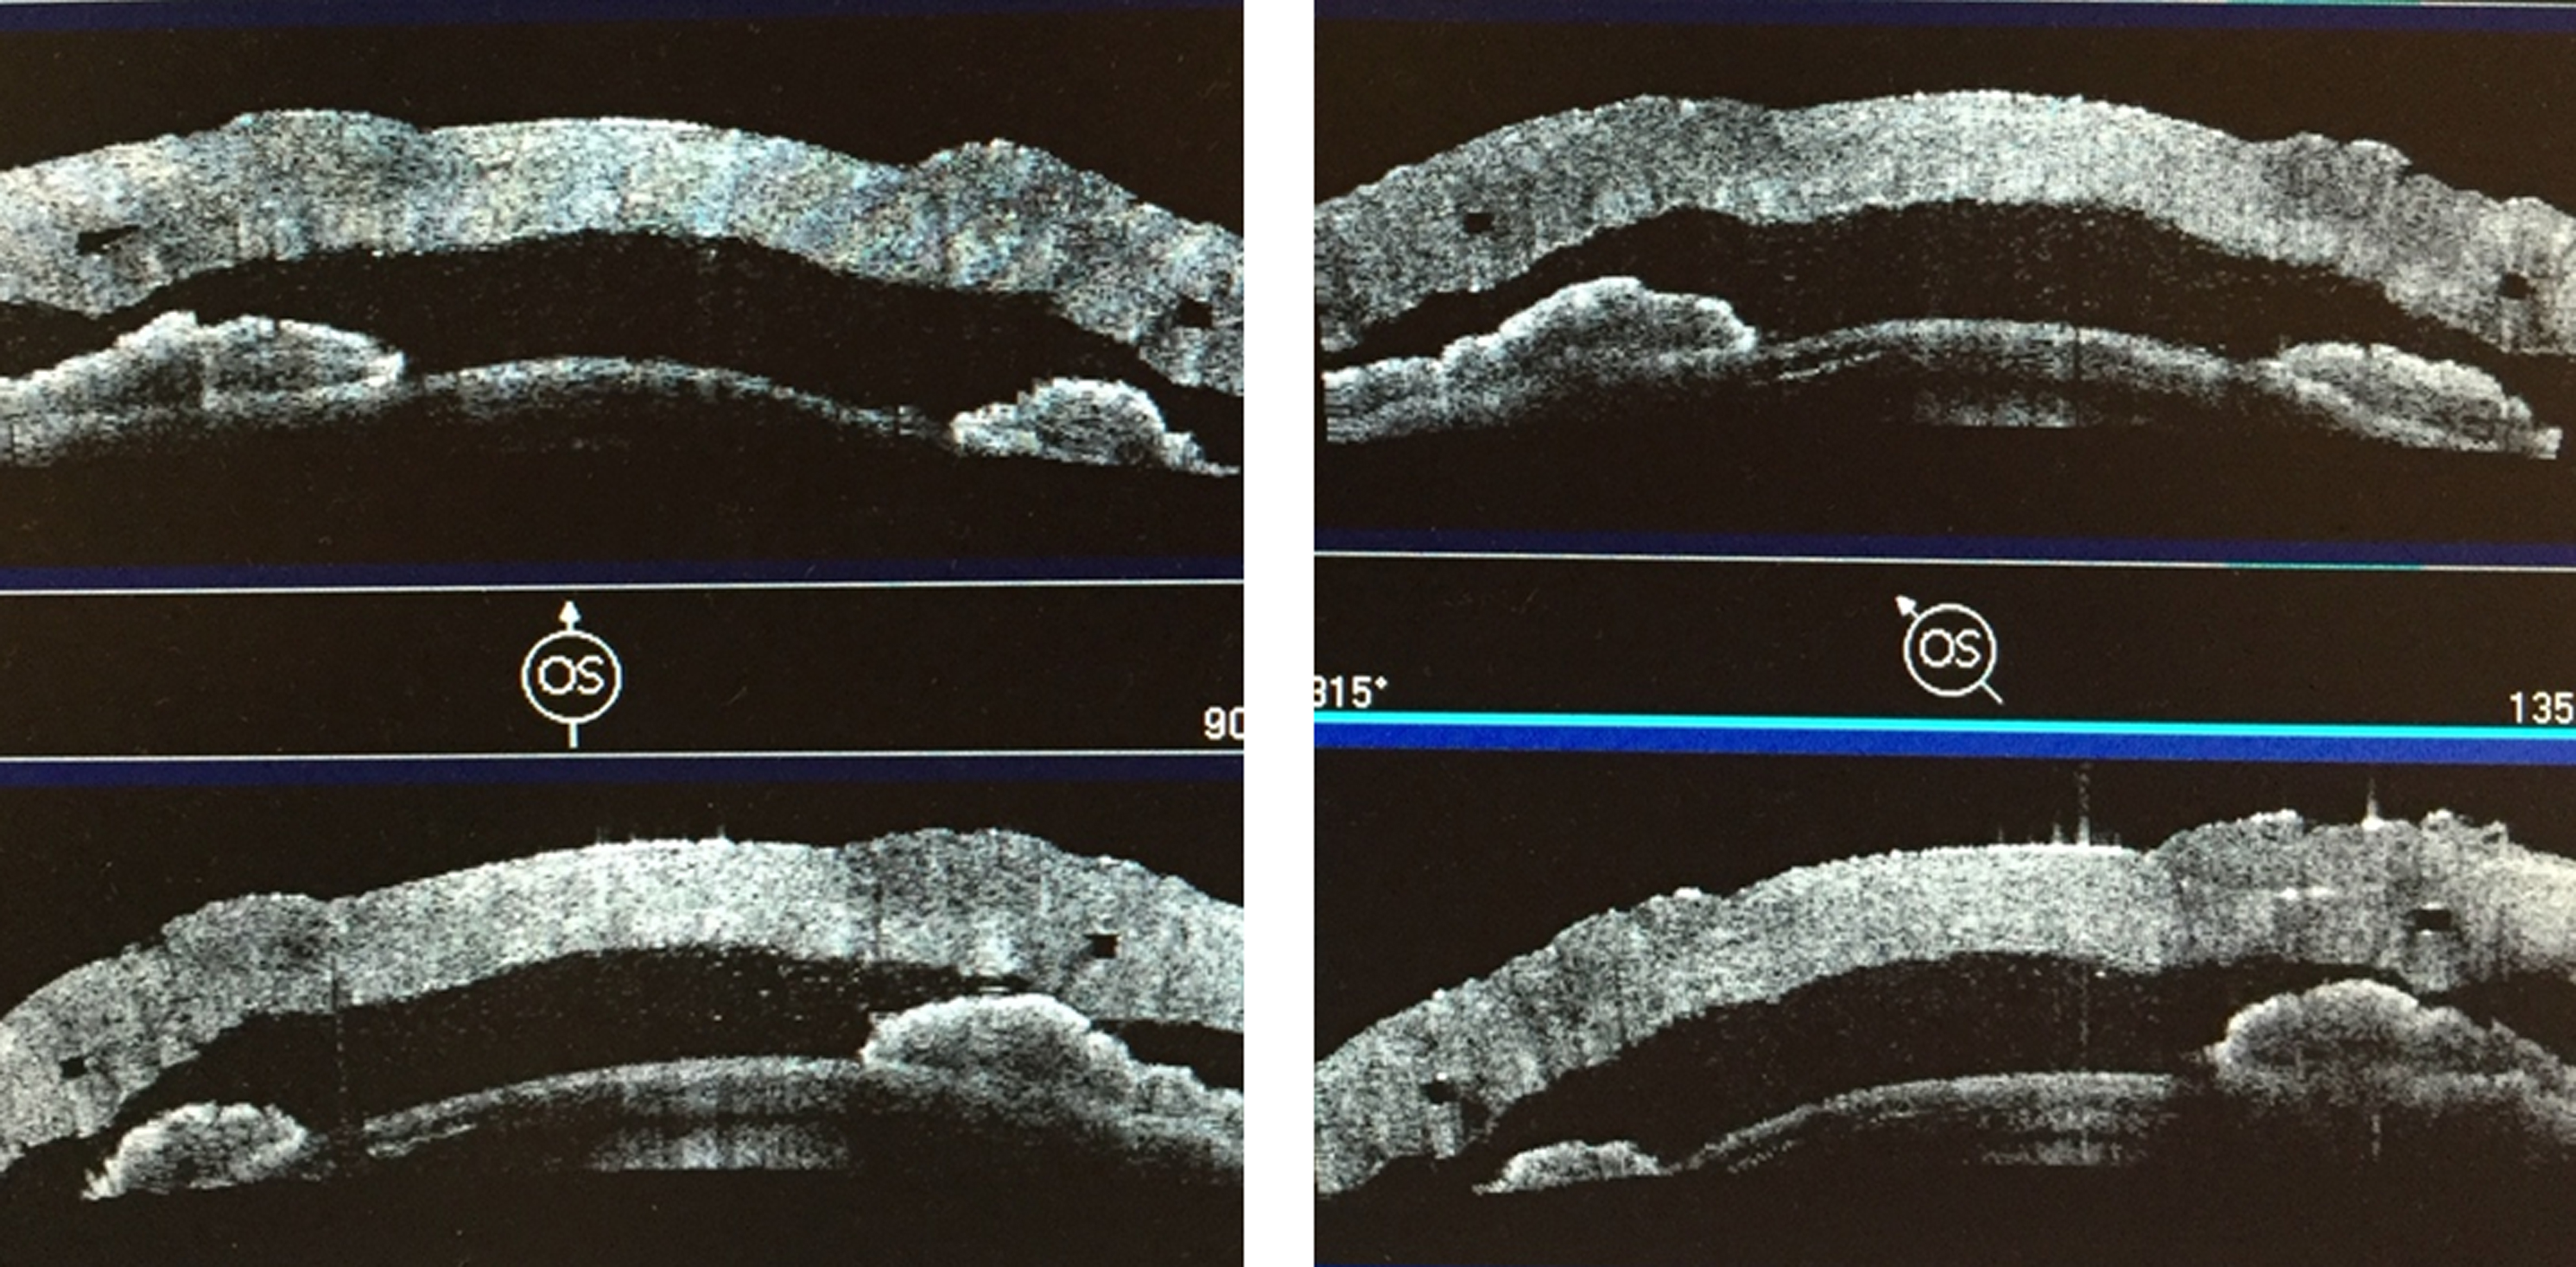

Результаты проведения модифицированной технологии сквозной фемто-кератопластики с имплантацией ИСК в эксперименте проводили с помощью оптической когерентной томографии переднего отрезка глазного яблока Visante ОСТ (Carl Zeiss Meditec, Германия). В ходе исследования оценивали положение ИСК (рис. 5), равномерность его залегания по глубине во всех сегментах.

Равномерность залегания ИСК оценивали путем определения глубины расположения его верхнего края в строме кадаверного глаза в 8 равномерно удаленных друг от друга точках по данным оптической когерентной томографии (ОКТ) (рис. 6), в среднем этот параметр составил (445,6 ± 14,9) мкм.

Рис. 5. Положение интрастрамального кольца в 4 меридианах в строме роговицы кадаверного глаза по данным оптической когерентной томографии

Экспериментальное моделирование на кадаверных глазах позволило разработать технику предлагаемой модифицированной сквозной фемто-кератопластики с имплантацией ИСК и алгоритм хирургического вмешательства [5]. По данным ОКТ переднего отрезка глазного яблока, интрастромальное кольцо располагалось равномерно во всех сегментах, без признаков его смещения. Использование параметров работы ФСЛ, разработанных совместно с производителем ФСЛ для проведения кератопластики, позволили выполнить качественное отделение роговичного диска без применения механического усилия во всех случаях.